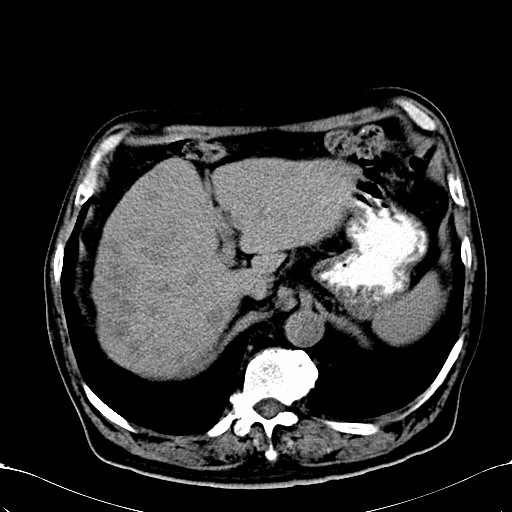

标题: CT28270:胰管扩张,肝多发占位 [打印本页]

标题: CT28270:胰管扩张,肝多发占位

患者,男,75岁。

考虑胰腺钩突癌并肝内转移,建议强化明确。

1)考虑胰头癌并肝脏多发性转移;建议行ct增强扫描检查。2)胃窦癌?建议行胃镜检查。

肝脏多方低密度结节,边缘模糊,考虑多发转移,胰管明显扩张,建议增强扫描钩突情况

肝脏多发低密度灶,胰头似呈低密度,胰管扩张,建议增强,

胰管显著扩张,但胆总管未见扩张征象,不太符合胰头占位!考虑慢性胰腺炎.胃窦占位并肝内转移可能!mrcp胃镜增强一起上!